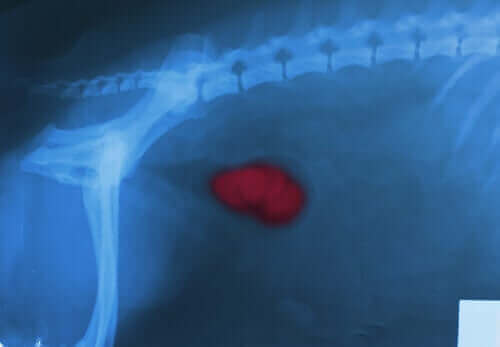

Svulst som en årsak til hematuri hos hunder

Svulster, enten godartede eller ondartede, er abnormale og overdrevne vekster i vev eller andre kroppsdeler. For eksempel prostatahyperplasi, hemangiom eller hemangiosarkom kan forårsake blødning.